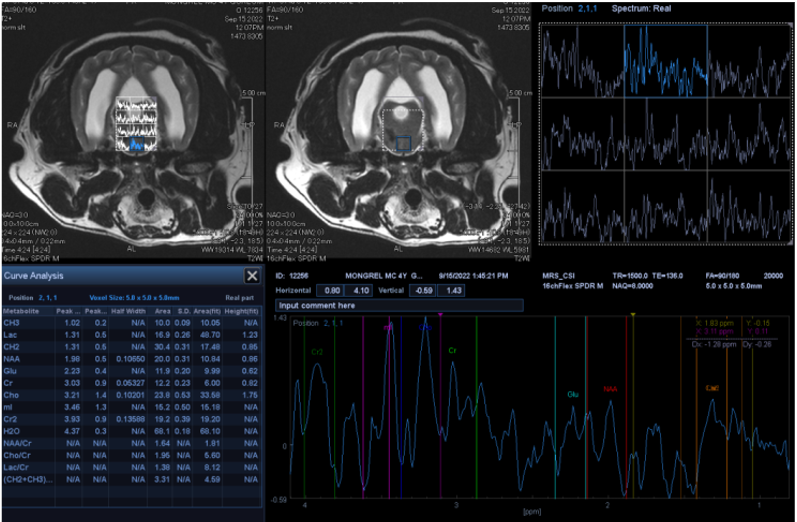

MR Spectroscopy (MRS) 기반 뇌 대사기능 평가

MRI 촬영과 동시에 MRS(자기공명분광) 평가가 가능하여, 구조적 이상과 대사적 변화를 한 번의 검사로 확인할 수 있습니다.

리더스 영상의학과는 다수의 MRS 검사 경험을 바탕으로, 뇌의 주요 대사물질(NAA, Cho, Cr 등)을 정밀 분석해 뇌 기능 저하와 대사 이상을 객관적으로 평가합니다.

전체 검사 시간은 약 40분 이내로, 일반 MRI 검사 시간 안에 뇌 구조와 대사 기능을 동시에 확인할 수 있습니다. 이를 통해 일반 MRI로는 확인하기 어려운 뇌 대사 변화를 통해 보다 정확한 진단이 가능합니다.

뇌 실질 내 염증(뇌수막염)과 뇌 종양 감별화

퇴행성 뇌질환(인지장애증후군) 의심되는 환자 뇌 대사 기능 평가

뇌 방사선 치료 후 뇌 실질 변화 정밀 평가

실제 환자 MRS 평가 사진